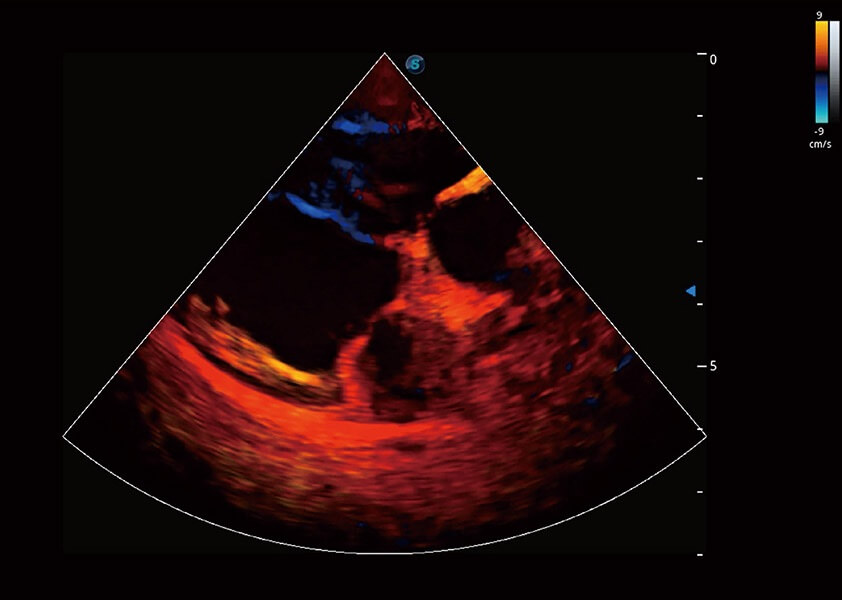

ProPet 60 作为一款高端台式动物超声设备,为动物医生的日常诊断提供了一系列贴合动物临床需求、解决临床实际问题的高级成像功能。凭借全系列高清探头,满足医生对腹部、心脏、生殖、浅表、肌骨等成像的所有需求,切实帮助您提升检查效率,提高诊断信心。

兽用彩色多普勒超声诊断系统

动物是人类最亲密的朋友和最值得信赖的伙伴。银河集团官网也一直致力于探索动物专用的超声影像解决方案。 全新推出的ProPet系列,是银河集团官网在动物超声影像智能化、专业化、精准化的一次跨越式革新。动物不能用言语来表述自己的不适,通过超声影像,ProPet系列搭建了动物医生与不同物种沟通的“桥梁”,为动物医生注入了“治愈之力”。